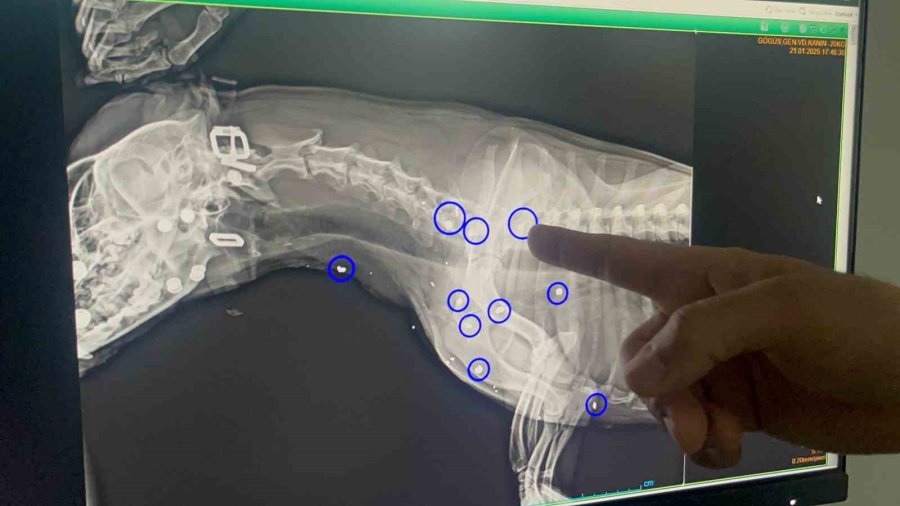

Tepebaşı ilçesi Aşağısöğütönü Mahallesi'nde sahipsiz köpek, hayvan severlerin iddiasına göre 21 Ocak tarihinde av tüfeği benzeri bir silah ile vuruldu. Vücudunun 12 yerine saçma değen ve yaralanan köpek özel bir veteriner kliniğinde tedavi alındı.

"İlk geldiğinde zaten saat 05.00 civarlarında geldi. Karnının tok olduğunu düşündüğümüz için anestezi uygulayamadık. Ertesi gün röntgeni çekildiğinde de 12 yerinde saçma yaraları olduğunu gördük. Hayati organlara çok yakın olduğu için saçmaları ne yazık ki alamadık. Şu anki süreçte de kalbinde bir büyüme olduğu için ne yazık ki anestezi uygulayamıyoruz, sonraki süreçte kurşun yaralarından dolayı zehirlenme var mı diye durumu mutlaka değerlendirip test ve kontrollerini yapacağız".